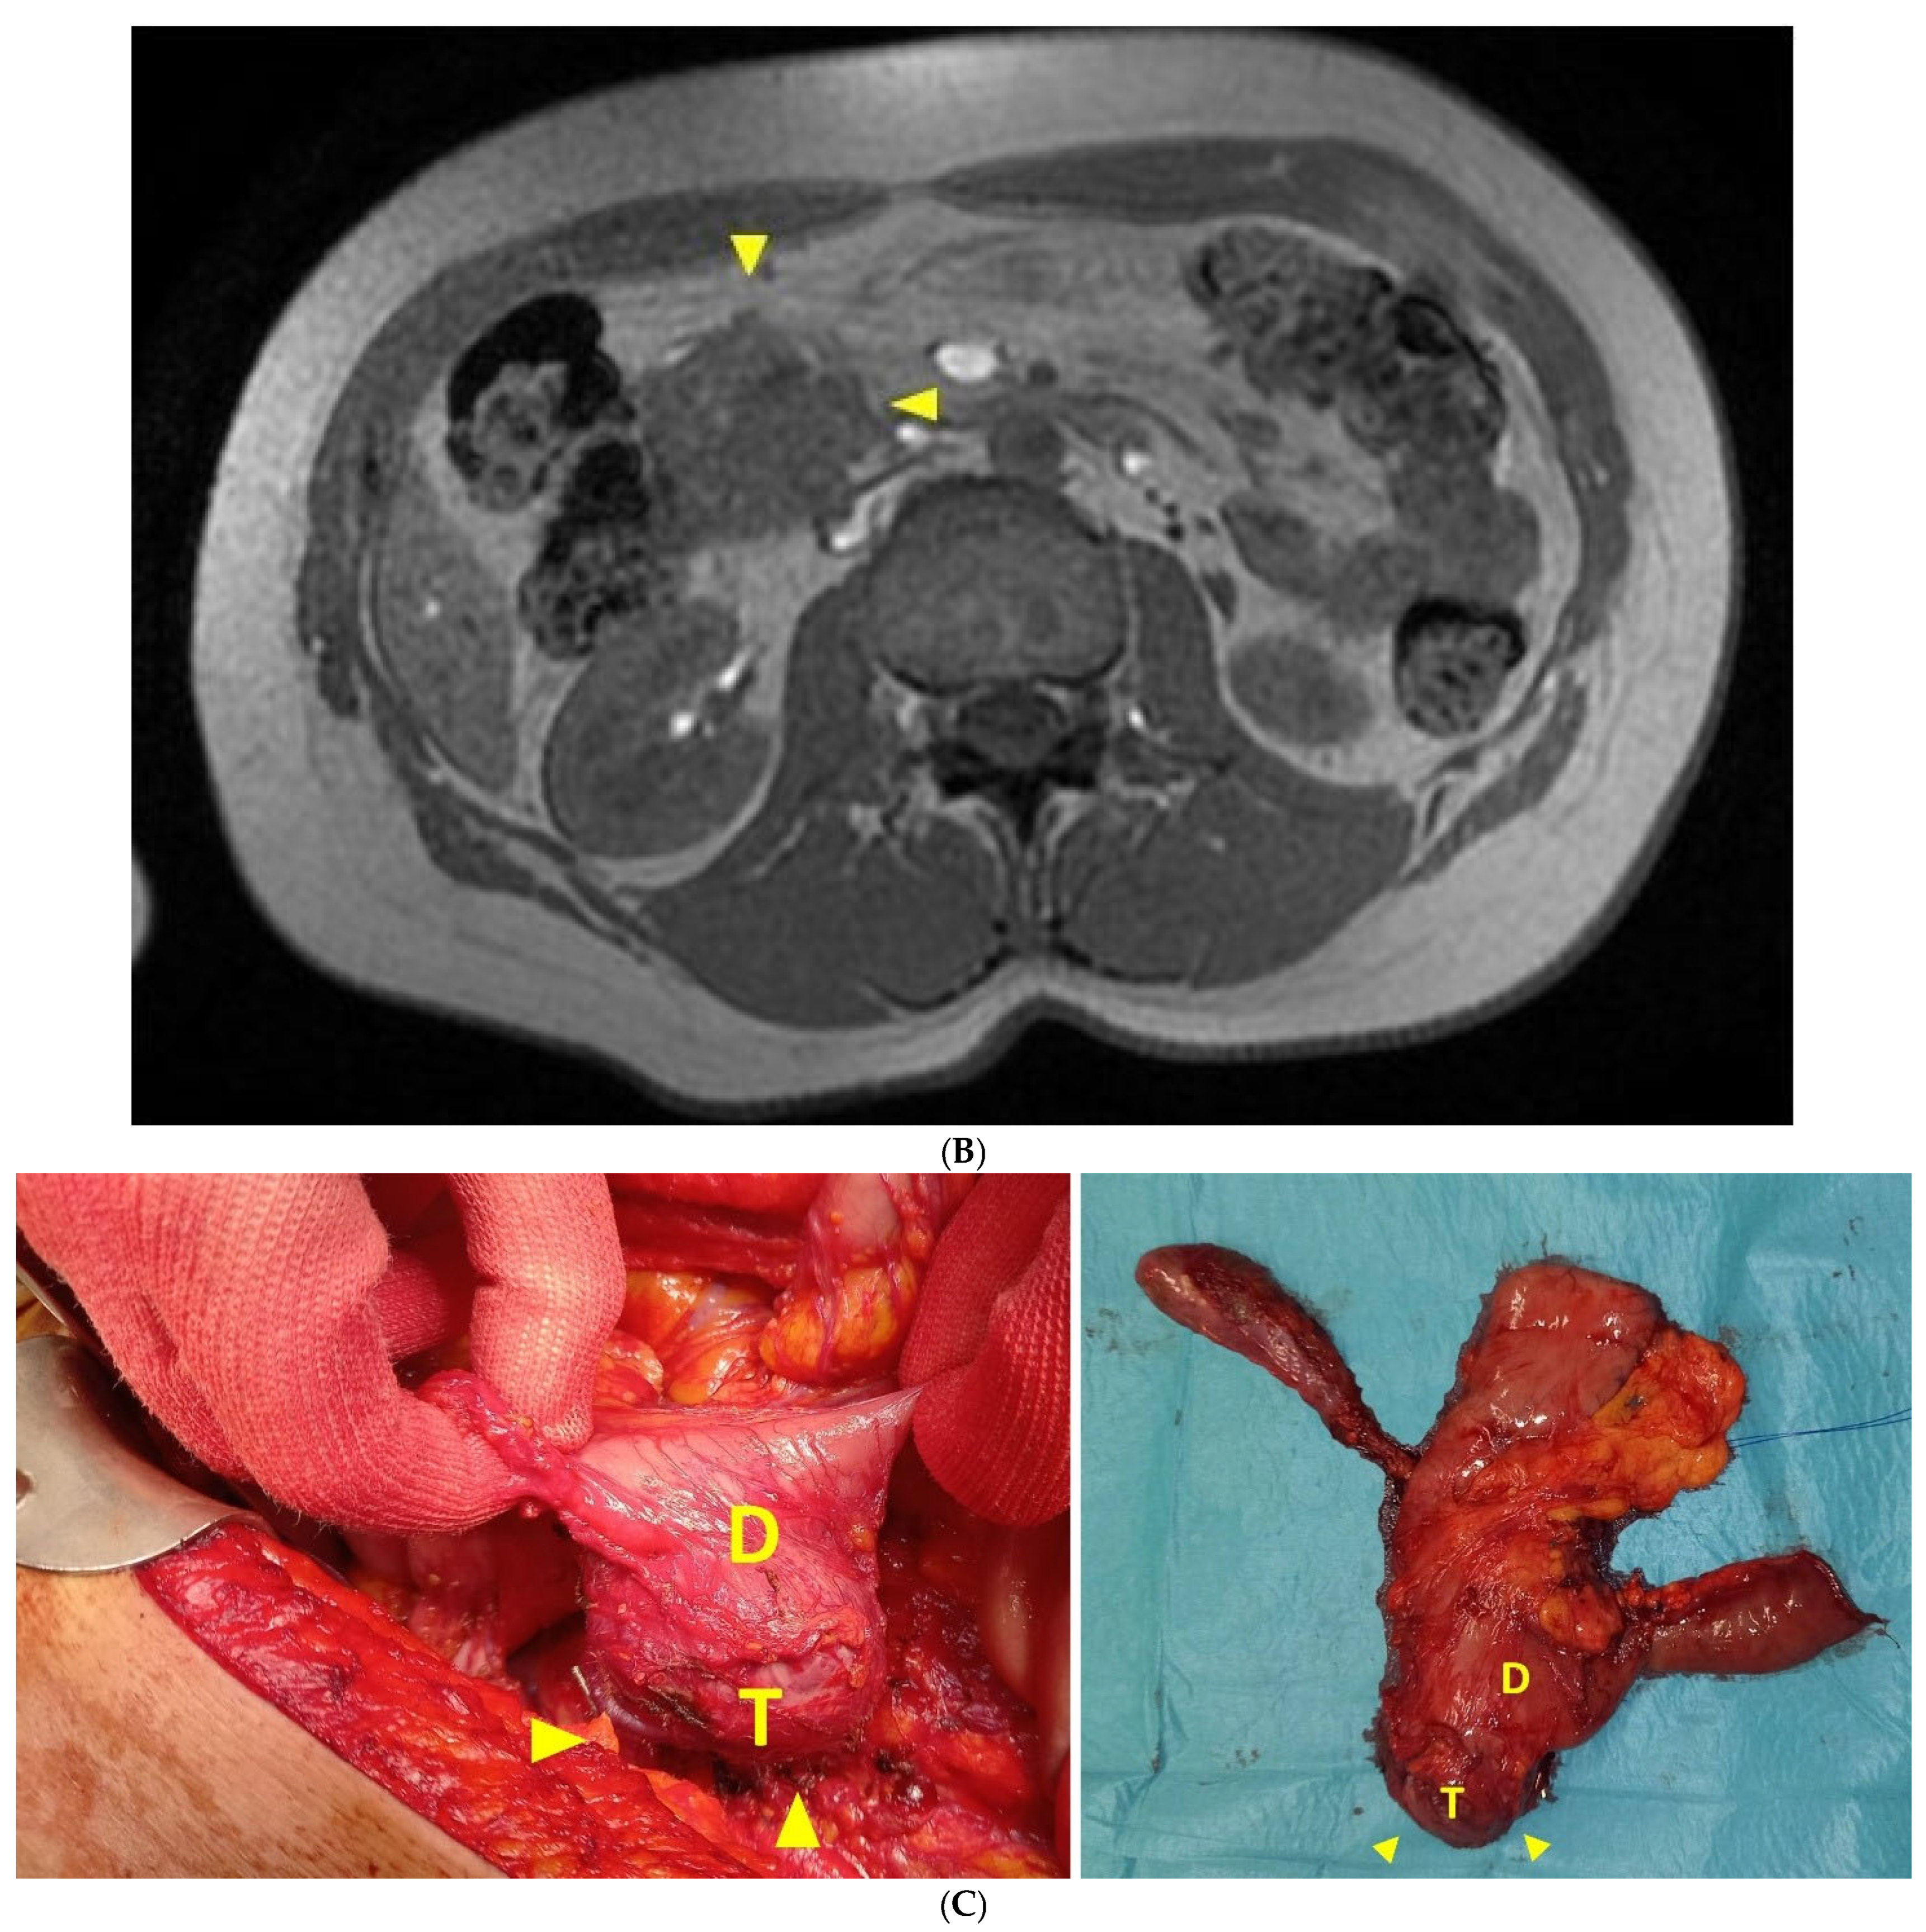

2.2. Case Report 2